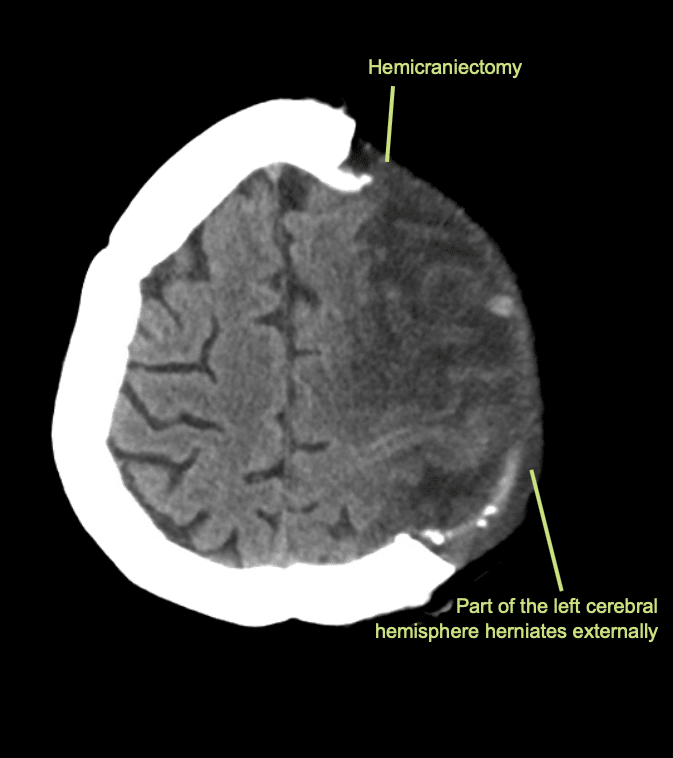

Immagini post operatorie